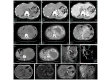

The present study aimed at identifying the clinical, radiological and pathological characteristics of retroperitoneal paragangliomas, and determining the association between the tumor features and the prognosis of patients following surgery. A total of 34 patients with retroperitoneal paragangliomas, who underwent resection between November 1999 and December 2015, were included in the present retrospective study. The patients' demographics, clinical symptoms and signs, tumor functional status, surgical procedure, intraoperative results, tumor pathology, radiological results, and postoperative survival time were recorded and analyzed. Of the 34 patients, the most common type of presenting symptom was abdominal mass (46%), followed by hypertension (39%) and abdominal pain (32%). Functional tumors occurred in 20 patients (59%). Computed tomography (CT) and magnetic resonance imaging revealed soft-tissue masses, with marked enhancement in the arterial phase, indicative of retroperitoneal paragangliomas. The preoperative CT diagnostic accuracy rate between 2010 and 2015 was markedly improved, compared with that between 1999 and 2009. The tumors were primarily located close to the renal arteries and veins surrounding the abdominal aorta and inferior vena cava. With the exception of one malignant paraganglioma, the majority of paragangliomas were positive for chromogranin A, S-100 protein, vimentin and heat-shock protein 90, and exhibited decreased expression of Ki-67 antigen and insulin-like growth factor 2. All tumors were completely removed by surgery. Distant metastasis, but not tumor size, functional status and local invasion, was markedly associated with survival. The preoperative diagnostic accuracy rate of retroperitoneal paragangliomas may be improved by focusing on the predilection sites and CT characteristics. In addition, immunohistochemical markers were useful to determine tumor malignancy. Complete surgical resection was appropriate for all patients and postoperative survival time was identified to be associated with tumor metastasis.